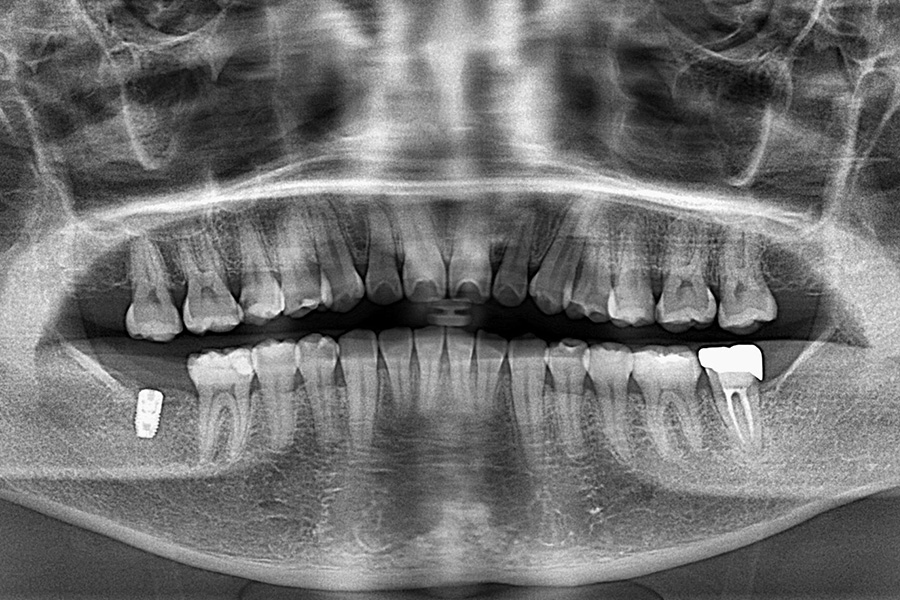

治療前

治療内容 右下7のインプラント治療(1本)